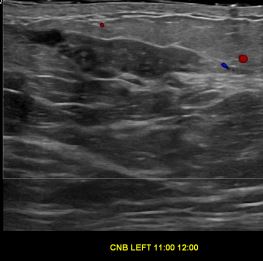

상기환자는 외부검사 이상소견으로 내원하신 30대후반 여성분으로 의심스러운 좌측혹 조직검사 시행해 유방암으로 진단되었습니다